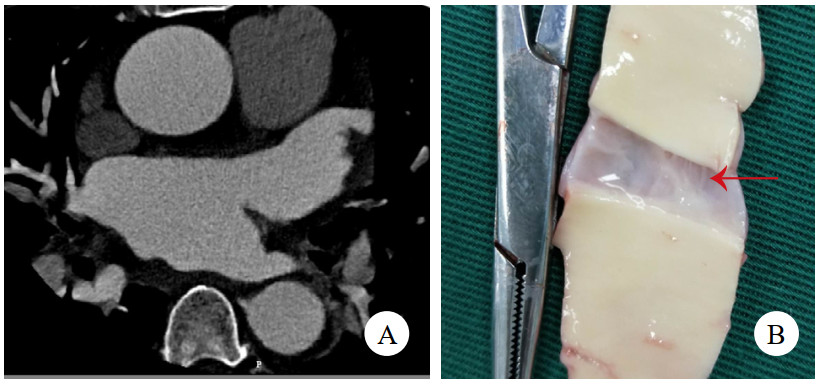

1 病例资料病例1,女,41岁,因“突发严重胸闷气促15 h”入院。发病后立即就诊于附近医院,查胸腹平扫CT提示急性肺水肿、双侧胸腔积液、心包积液,查血红细胞计数3.38×1012/L,肌酐369 μmol/L,乳酸11.7 mmol/L,钠尿肽超过检测上限,立即转诊至本院。考虑存在急性多脏器衰竭,立即收入重症监护室,因少尿予连续肾脏替代治疗。右侧胸腔穿刺引流液红细胞计数高达0.22×1012/L。床边经胸超声心动图(transthoracic echocardiography, TTE)未见主动脉病变,但见左心室弥漫肥厚符合高血压性心脏病,心包大量积液伴血块,且出现心包填塞,紧急行心包穿刺,但置管后引流不畅。因心包积液病因不明,且回顾前平扫CT可见升主动脉壁局部密度增高(图 1A),急查主动脉CTA,但影像科对升主动脉根部管壁褶皱情况考虑为搏动伪影。后查经食管超声心动图(transesophageal echocardiography, TEE),清晰可见升主动脉直径38 mm,距主动脉瓣环约16 mm处有飘动纤细光带,考虑升主动脉LIT(图 1B、图 1C)。遂行急诊开胸手术,术中见心包腔内大量积血并血块,升主动脉外膜血肿延入肺动脉外膜至右侧肺门。建立体外循环后,在头臂干开口近侧阻断升主动脉,顺行灌注心脏停搏液良好,纵行切开升主动脉,见左右冠瓣上方横行内膜裂口,中膜无假腔形成,冠状动脉开口、主动脉瓣无病变。用26 mm人工血管置换升主动脉,手术顺利。术后复查TTE见人工血管通畅、形态良好。回顾并重建术前主动脉CTA,曲面重建可见内膜片(图 1D),该处主动脉直径为37 mm。患者术后肾功能衰竭持续,规律随访血透,6个月后失访。

| 注:A为平扫CT,箭头示升主动脉壁增厚、密度增高;B为TEE舒张期,箭头示飘动纤细光带;C为TEE收缩期,箭头示飘动纤细光带;D为主动脉CTA,曲面重建,箭头示内膜片 图 1 例1患者两次CT及术前TEE影像 |